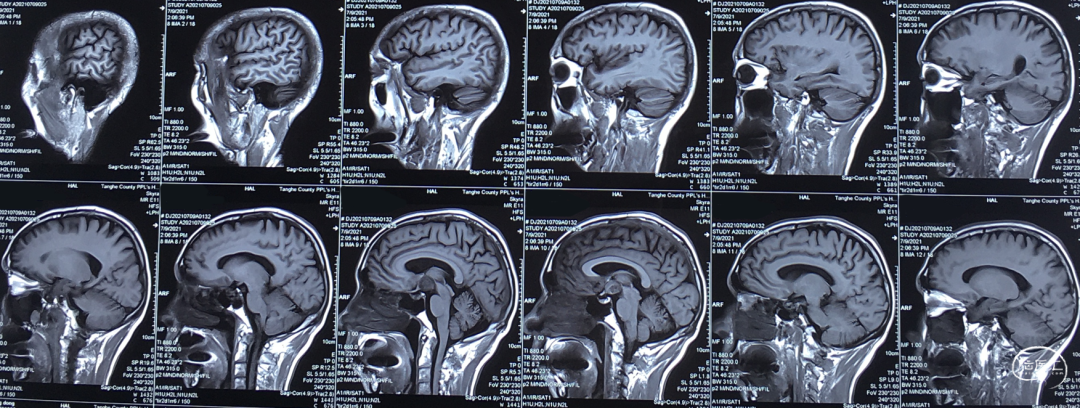

术前影像学检查

NCT 2020-07-14

NCT 2021-07-08

CTA 2021-07-08

MRI-T1 2021-07-08

MRI-T2 2021-07-08

MRI-Flair 2021-07-08

MRI-DWI 2021-07-08